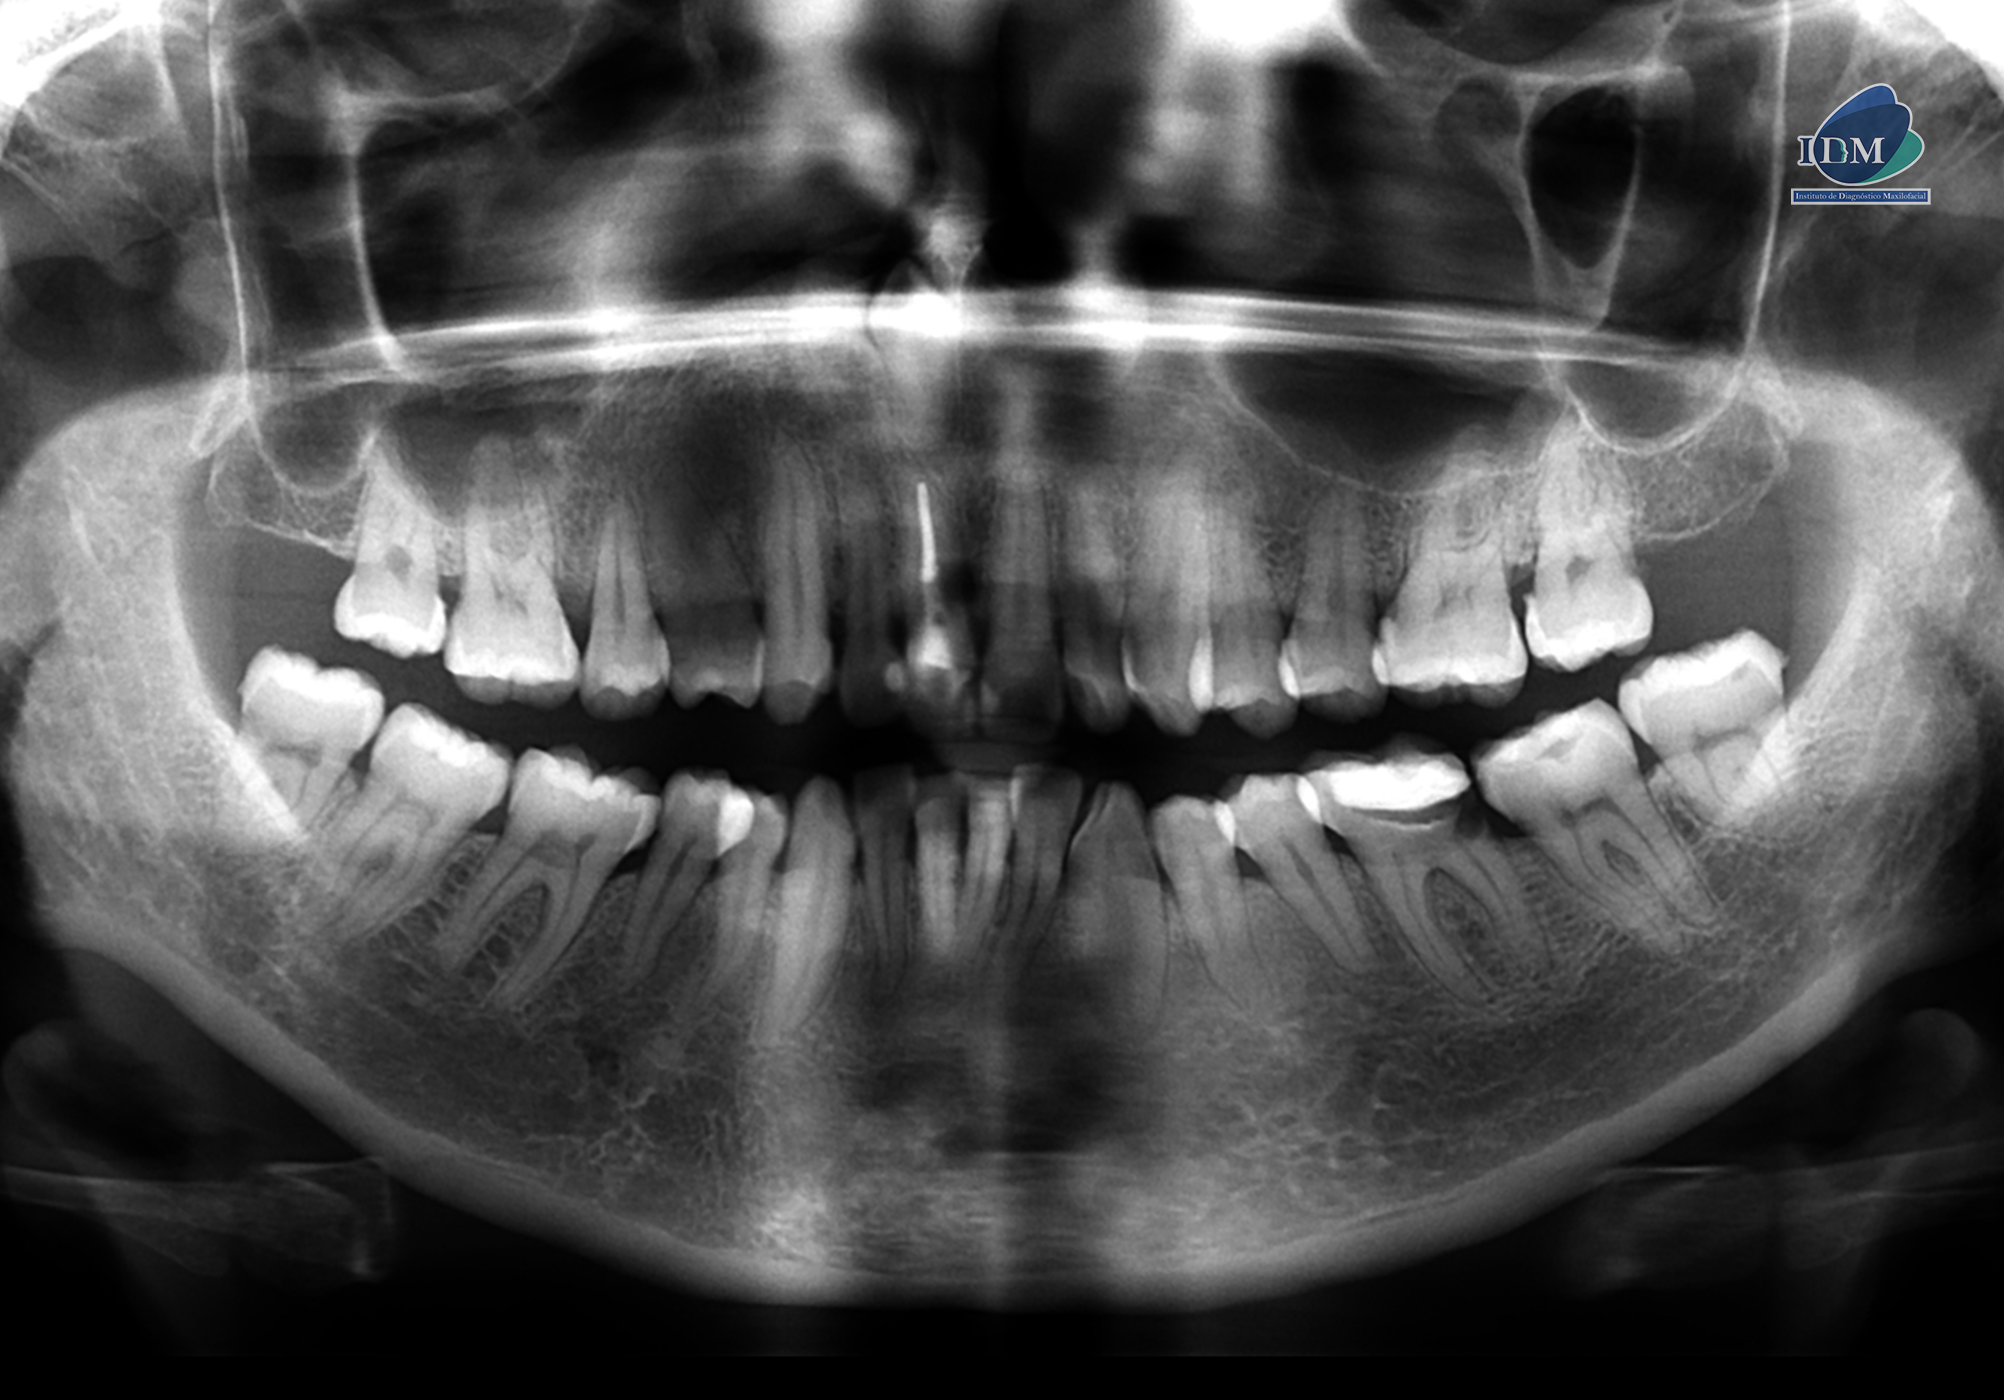

Paciente femenino de 43 años acude al Instituto de Diagnóstico Maxilofacial (sede Miraflores) para evaluación generalizada.

A la evaluación de la radiografía panorámica se evidencia un diente supernumerario retenido en posición invertida en sector anterosuperior.

Radiografia Panorámica

Así mismo en la tomografía volumétrica de haz se evidencia que dicha pieza está ubicada en zona vestibular. Contactando con el conducto nasopalatino, próximo a ápice de la pieza 11 y con el segmento coronario contactando con piso de fosa nasal derecho.